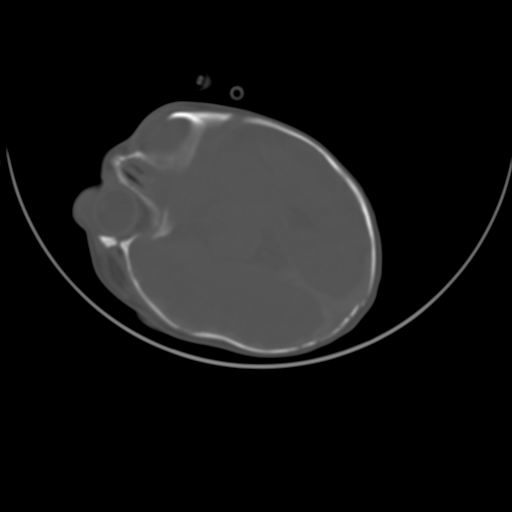

标题: PED0836: 新生儿

双侧硬膜下血肿并蛛网膜下腔出血。

双侧硬膜下血肿并蛛网膜下腔出血

硬膜下及蛛网膜下腔出血。

hie 蛛网膜下腔出血,硬膜下血肿。

hie;双侧硬膜下血肿并蛛网膜下腔出血

hie,双侧硬膜下血肿并蛛网膜下腔出血

双侧硬膜下血肿并蛛网膜下腔出血,考虑维生素k缺乏引起.

较大范围出血,应考虑维生素k缺乏引起,结合临床吧。

好像脑实质没有明显低密度影,各位大侠怎么支持hie呢?